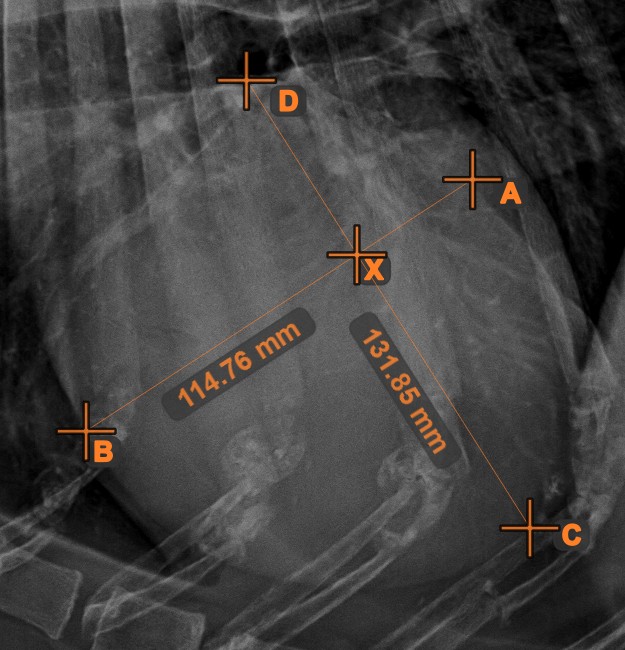

Quickly and accurately locate and mark the intersection point between two existing lines by using the Line Intersection tool.

Select the tool from the left toolbar and assign it to one of the available mouse buttons. Select two lines that have already been drawn on the scene to complete the measurement. The intersection point of the line will be automatically calculated and marked on the scene. The intersection point of two lines will always be marked with the letter X.

If two lines do not intersect directly, the intersection point of their extended projections on the scene will be marked.